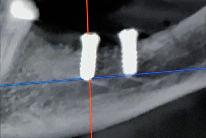

> Präoperativ wurde im Sinne eines Backward Planning erst die spätere Implantatposition und in Kenntnis dieser, die Ausdehnung des Titangitters festgelegt

> Hierbei wurde festgestellt, dass sich zum einen das Foramen mentale direkt im Augmentations und Implantationsbereich befindet und zum anderen der Verlauf des Nervus alveolaris

inferior, trotz Augmentation, nur relativ kurze Implantate zulassen wird

> Bei der digitalen Planung des Gitters wurde dieser Aspekt besonders berücksichtigt und zudem auf die Lage des Foramen mentale speziell geachtet. Das Gitter wurde im Austritts bereich ausgespart, um eine Traumatisierung zu vermeiden.

3 | Patientenspezifische Anforderungen (z B Foramen mentale) werden für die geplante Knochenaugmentation durch die Customized Bone Regeneration (CBR®) berücksichtigt.